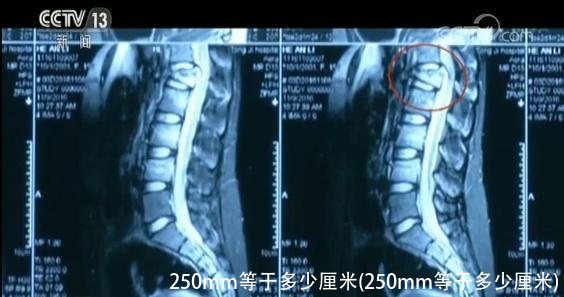

华中科技大学同济医院创伤外科主任医师 宋先舟:检查的时候就发现她双下肢的肌力还是差一些,再就是会阴部的感觉减退,X射线检查和磁共振的检查证实腰椎的骨折,腰1的压缩性骨折和脊髓挫伤。

受伤后的两年间,小雨先后经历了两次手术,身体内植入了六颗钢钉,骨折的腰椎才得以固定。

即便如此,小雨的马尾神经,由于骨折的压迫,受损严重,已经无法完全恢复。